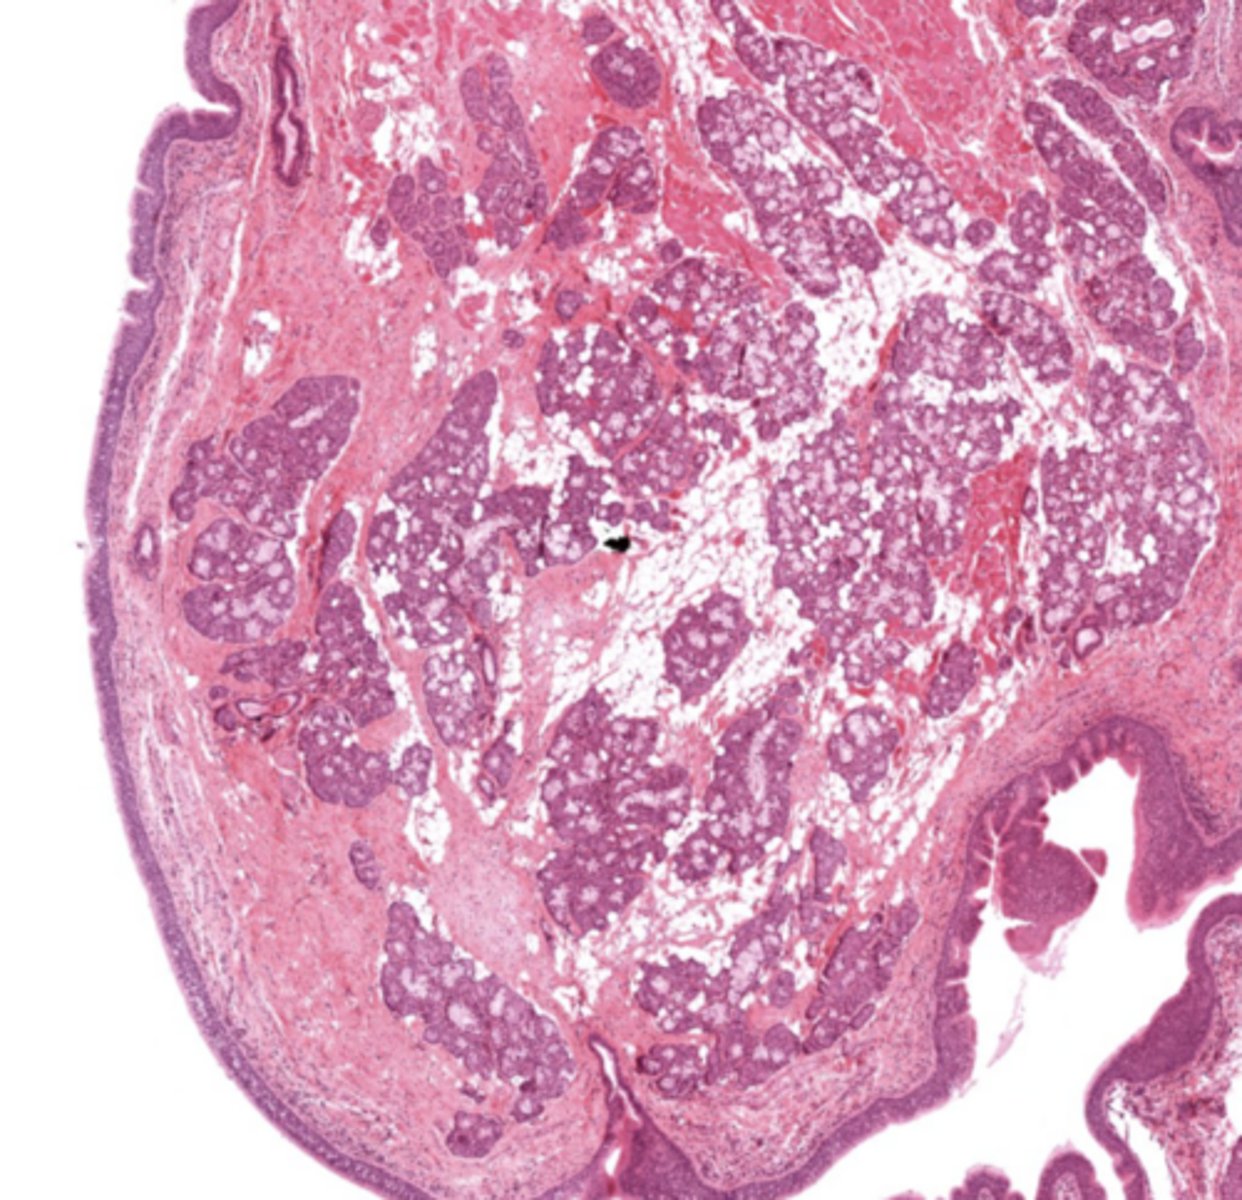

What tissue composes the vestibular folds?

Loose connective tissue with glands and lymphoid aggregations.

What epithelium covers vestibular folds?

Respiratory epithelium.

False cords of the larynx

Identify the image